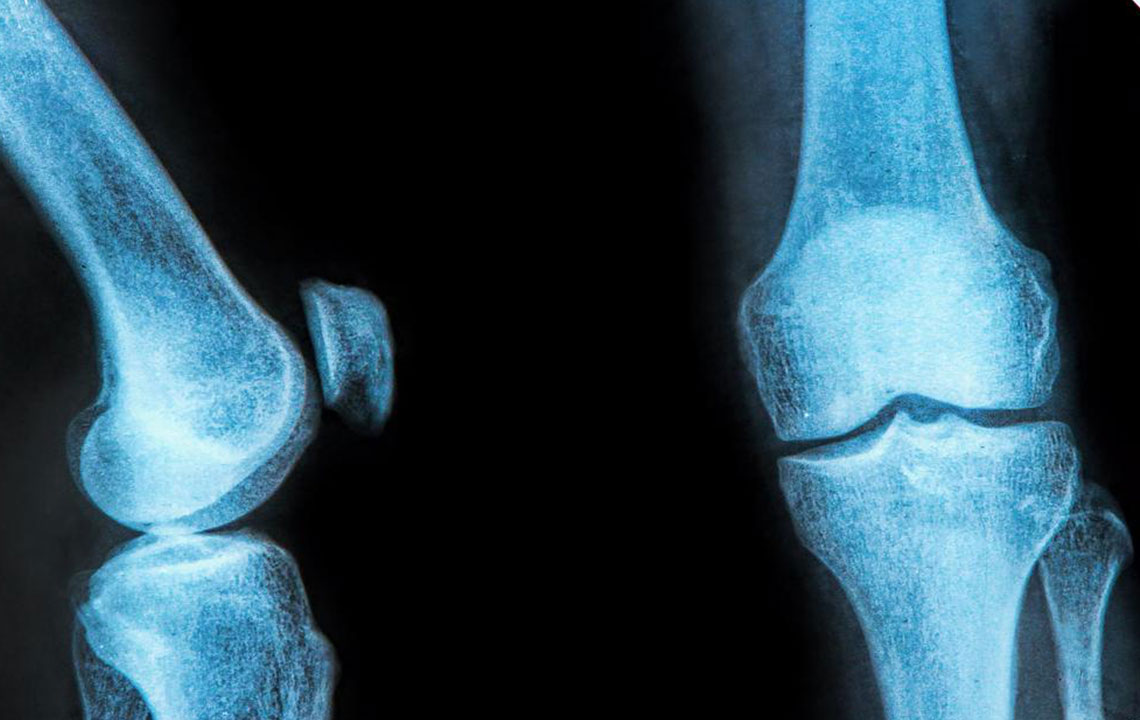

The rubbery C-shaped disc cushioning your knee is a meniscus. There are two menisci in each knee. One at the inner side and the other on the outer side. It is this meniscus that helps to keep your knee steady. It balances your body weight around your knee. If there is a tear in the meniscus, you will experience a lot of pain. It will also prevent the proper functioning of your knee.